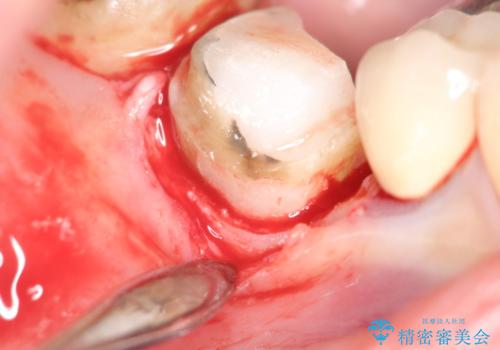

【外部吸収】根管治療、外科治療からのオールセラミッククラウン

- 歯肉の腫脹と被せ物の不適合を主訴に来院されました。

根管治療後、外部吸収を認めたため歯周外科を行ない歯冠修復を行なっております。